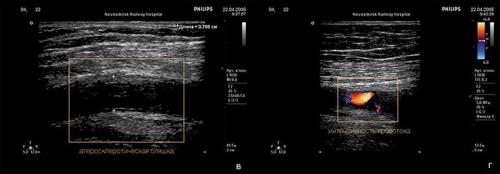

Морфологическим «носителем» атеросклероза являются так называемые атеросклеротические бляшки: плотные образования круглой или овальной формы, белого или желтовато-белого цвета, которые, возвышаясь над поверхностью внутренней оболочки сосудов, суживают их просвет. Наиболее часто фиброзные бляшки обнаруживаются в брюшной аорте и в отходящих от нее ветвях, а также в артериях сердца, мозга, почек, нижних конечностей, сонных артериях и др.